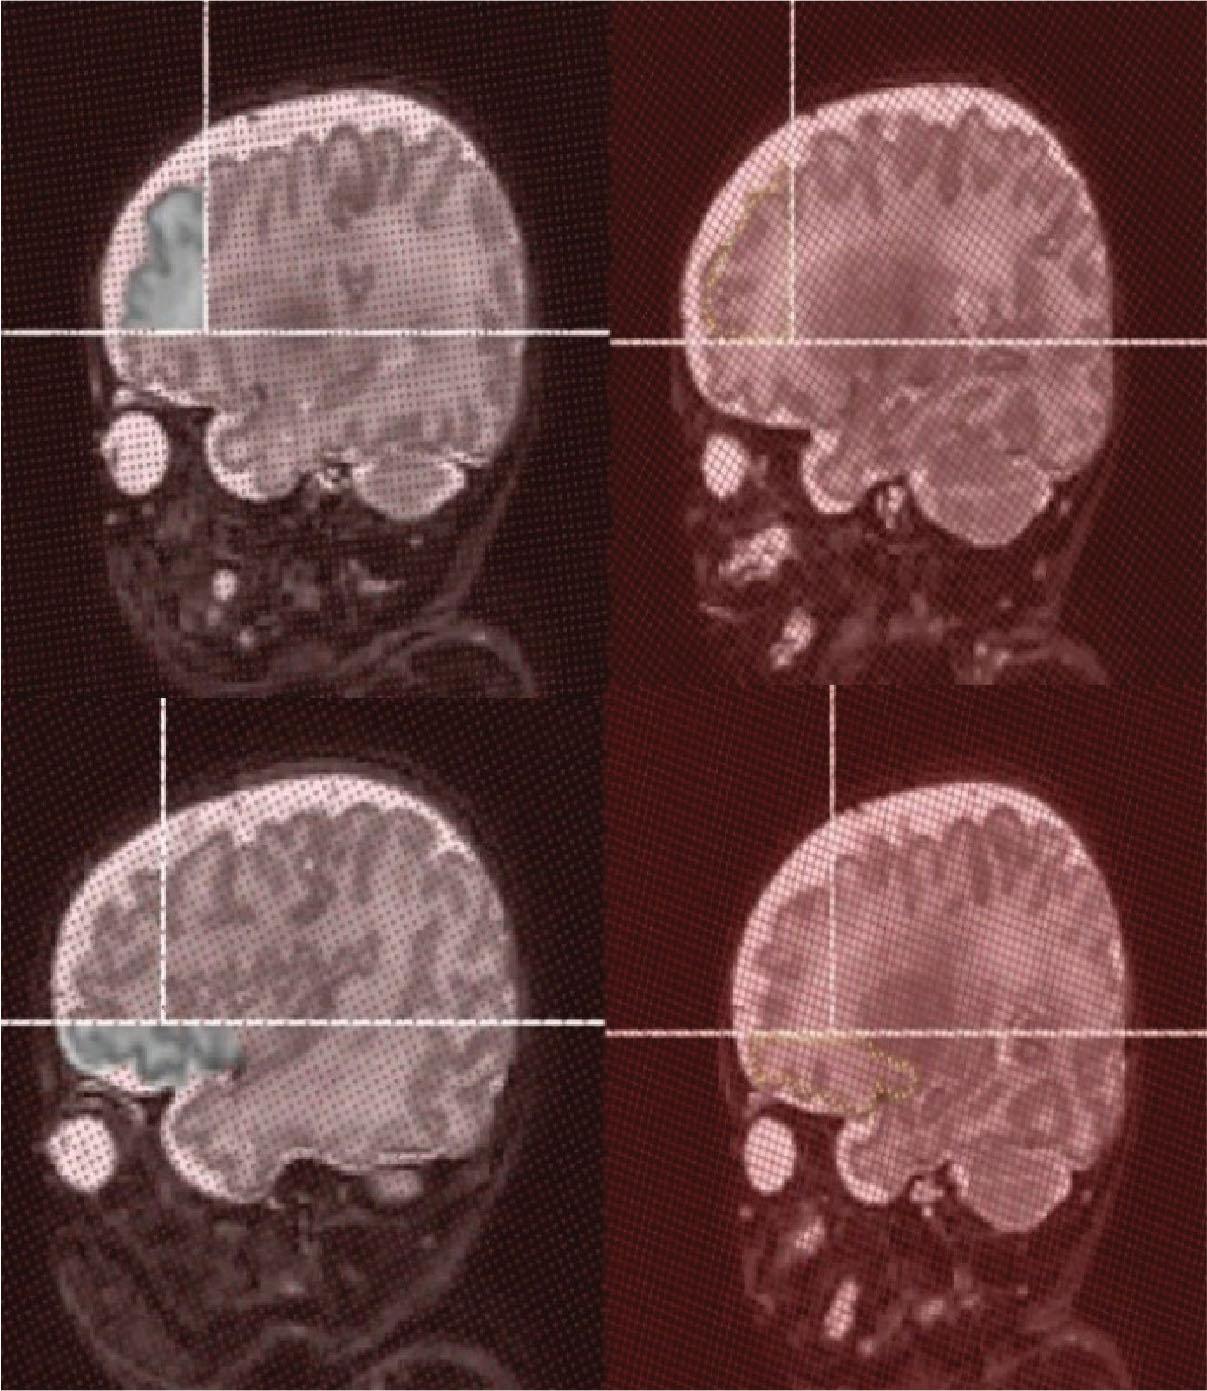

Figure 1.